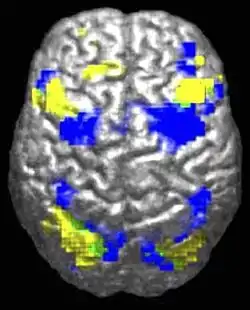

Des différences au niveau du cerveau ont été observées chez les personnes autistes, apportant une signature anatomique à la définition antérieure par des critères cliniques. Les études en neurosciences ont montré des différences dans l’organisation du cortex[29],[30], au niveau des dendrites (arborescences des neurones) et des synapses (connexion entre neurones), voire des modifications plus larges de structures cérébrales. Il est possible que les différences corticales apparaissent au cours d'un stade de développement anténatal[29].

En corrélation avec les différences fonctionnelles observées au niveau comportemental, les études d'Eric Courchesne et de son équipe relèvent que les enfants autistes ont un nombre de neurones plus élevé de 67 % en moyenne dans le cortex préfrontal[31], et une croissance cérébrale plus importante que la moyenne au niveau des lobes frontaux, ce qui s'est traduit dans la littérature scientifique antérieure par des observations de périmètre crânien plus élevé[32].

Cependant, le , dans une étude basée sur des données par imagerie par résonance magnétique (IRM), des chercheurs de l'Université Ben-Gourion du Néguev et de l'Université Carnegie-Mellon (États-Unis) ont estimé que les différences anatomiques entre le cerveau de personnes autistes de plus de 6 ans et celui de personnes du même âge non autistes sont indiscernables[33],[34]. Pour arriver à ce résultat, ces chercheurs ont utilisé la base de données Autism Brain Imaging Data Exchange (ABIDE), qui a permis pour la première fois de procéder à des comparaisons de grande échelle de scanners IRM entre des groupes de personnes autistes et des groupes contrôle[35]. Cette base de données est une collection mondiale de scanners IRM de plus de 1 000 personnes, pour la moitié autistes, âgés de 6 à 35 ans[36].

L'Institut de neurosciences de la Timone (Marseille, France) a identifié un marqueur anatomique spécifique de l'autisme, détectable par IRM et présent dès l'âge de deux ans. Ce marqueur consiste en un plissement spécifique du cortex cérébral. Il est appelé « racine du sillon »[37],[38],[39].